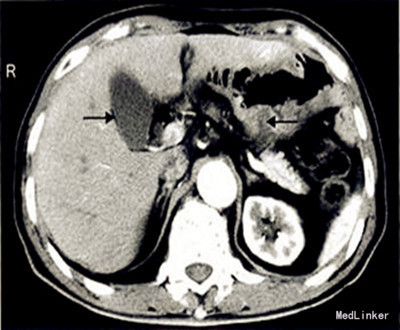

查体:腹部平坦,中上腹见一长约15 cm手术切口瘢痕,愈合良好,未见胃肠型及蠕动波,无腹壁静脉曲张,腹肌无明显紧张,腹上区和脐区轻压痛,无反跳痛,未触及包块,肝脾肋下未触及,墨菲征阴性,肝上界位于右锁骨中线第5肋间,肝区和双肾区无叩击痛,移动性浊音阴性,肠鸣音3~5次/min,未闻及气过水声及血管杂音;肛门指诊未触及包块,指套退出无血染。 辅查:腹上区CT检查:原胃大部分切除术后改变,残胃充盈不佳,壁稍增厚(图)。AFP 2.08μg/L,CEA 7.26μg/L,糖类抗原CA72-4 3.12μg/L。